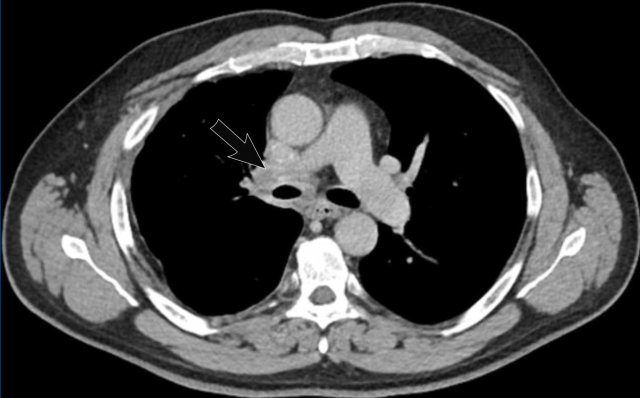

Image

Tracheobronchial

papillomatosis with lung involvement in a 54 y.o male, showing two papillomas

in the trachea.

Continue with the lung window...

The image shows multiple cystic lesions in both lungs (arrowheads).

In rare cases extension into the lung parenchyma can occur, showing cystic nodules most often in the dependent apical segments of the lower lobes. There is a small risk of malignant transformation from squamous cell papilloma into squamous cell carcinoma.